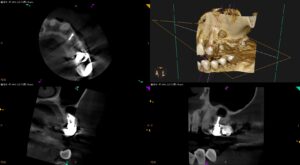

紹介患者さんの治療。 主訴は、 どこの歯科医院に行っても歯が折れているので抜歯と言われるが残したい…何とかならないだろうか。。。 である。 歯内療法学的検査(2025.7.28) #11 Cold+1/3, Perc.( … 続きを読む どこの歯科医院に行っても歯が折れているので抜歯と言われるが残したい…〜#12 Apicoectomy